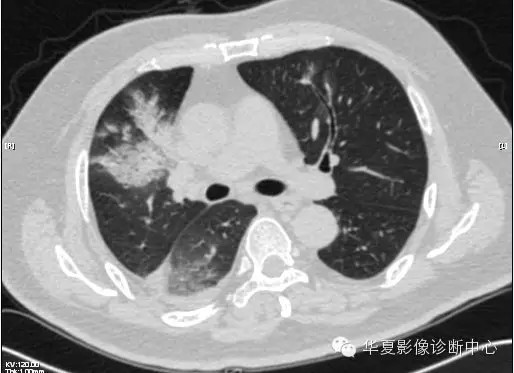

【病例学习】甲型H7N9禽流感一例

男性 63

发热咳嗽5天

2013-4-5拍片示右肺实变,收入院,追问病史,发病期间肌肉酸痛,头痛,无腹痛腹泻,无明显胸闷气急,无意识改变。有高血压病史,无其它病史。

2013-4-7CT进一步检查。

最终诊断:H7N9。